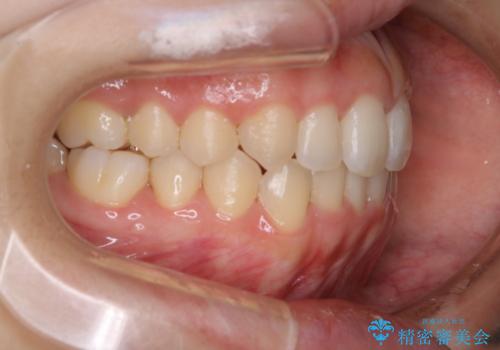

オープンバイト(開咬)を非抜歯インビザラインで治す

- 上下のがたつきを気にされてご相談にいらした患者さまです。

症状としてはオープンバイト(開咬)があり、舌癖も見られました。

オープンバイトの方への治療は、通常抜歯を行いワイヤーによる矯正治療を行うことが多いですが、今回はインビザラインの特性を生かし、非抜歯にて綺麗な歯並びを作ることが出来ました。